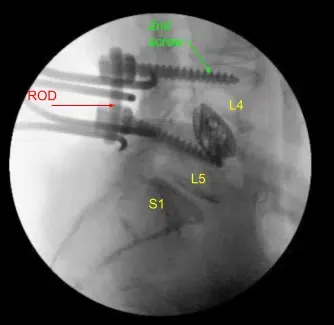

Given the concern for the implant in the prone position and our feeling that the endplates may have fractured more, we exposed the transverse processes for L4 and L5 and used the drill to create pilot holes in the pedicle on the left side at L4 and L5. Under fluoroscopy, we guided probes through the pedicles and tapped each pedicle, then placed pedicle screws into L4 and L5.

These screws were stimulated, and checked under fluoroscopy, and then a rode was placed and cap screws were given a final tightened. On the right side and left side, we decorticated the facets and transverse processes and placed our fusion mass for arthrodesis.